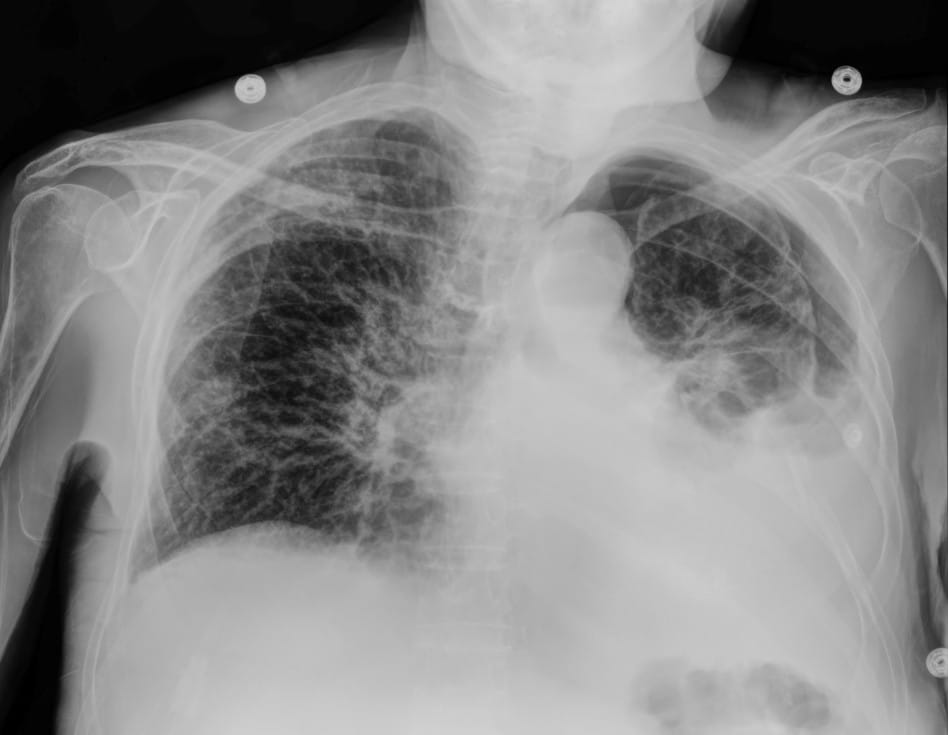

Conventional radiography compresses all anatomical information into a single image. In complex clinical environments, overlapping structures may obscure clinically relevant findings.

Spectral X-ray imaging separates bone and soft-tissue information from a single exposure, producing multiple image outputs while maintaining the same workflow as standard radiography.

Reveal™ 35C detectors use SpectralDR® technology to acquire multiple spectral images from a single X-ray exposure.

Each exposure produces:

- a conventional digital radiography image

- a bone image

- a soft-tissue image

These images allow clinicians to separate overlapping anatomical structures and visualize areas that may be less visible in conventional radiographs.

Unlike traditional dual-energy imaging techniques that require multiple exposures, SpectralDR captures these images simultaneously with a single exposure, eliminating motion artifacts and maintaining the same clinical workflow as standard portable radiography.

Soft-tissue images can reduce rib overlap and may improve visualization of pneumothorax during bedside chest X-ray examinations.

Spectral imaging can enhance visualization of lung opacities by separating bone from soft tissue, potentially improving evaluation of pneumonia and other lung conditions.